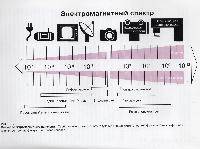

Магнитно-резонансная томография (МРТ):один из самых эффективных методов диагностики заболеваний